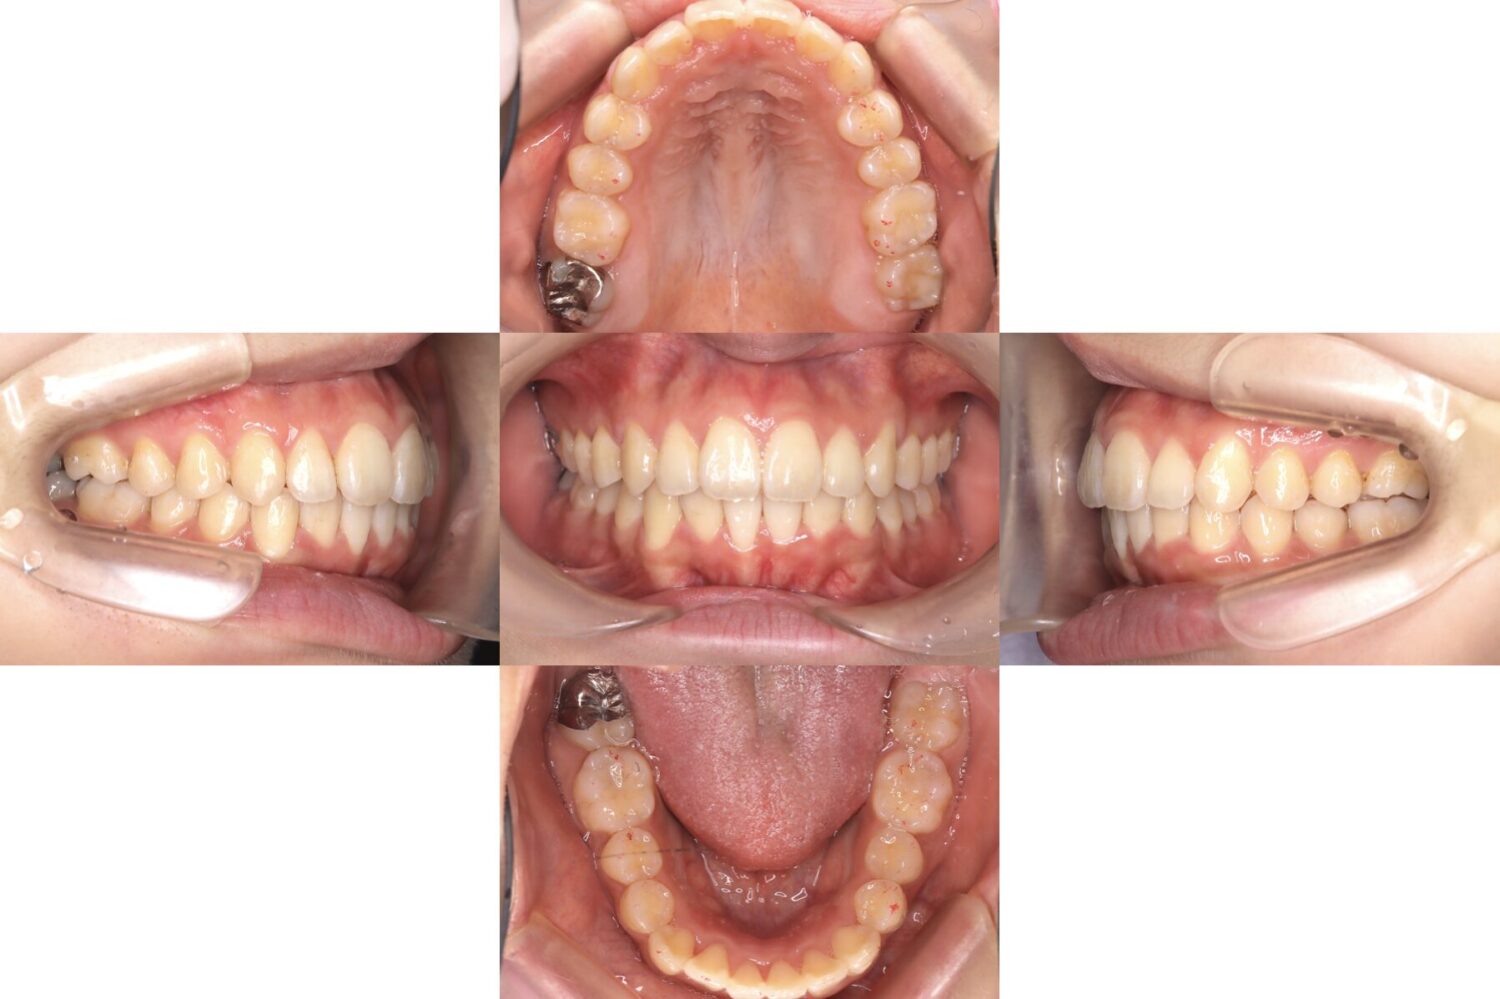

治療前後の比較|歯列全体のバランスが改善

治療前後を比較すると、前歯の突出感、歯列のガタつき、歯の並びのバランスが改善していることが分かります。

歯並びが整うことで、見た目だけでなく、歯磨きのしやすさや噛み合わせの安定にもつながります。

治療後は、全体的な歯列のガタつきが改善され、前歯の突出感も大きく軽減しました。

歯が整ったことで、歯磨きもしやすくなり、虫歯や歯肉炎の予防にもつながりやすい状態になっています。

また、口元の印象も自然で柔らかくなり、笑顔にも自信を持っていただきやすい仕上がりとなりました。